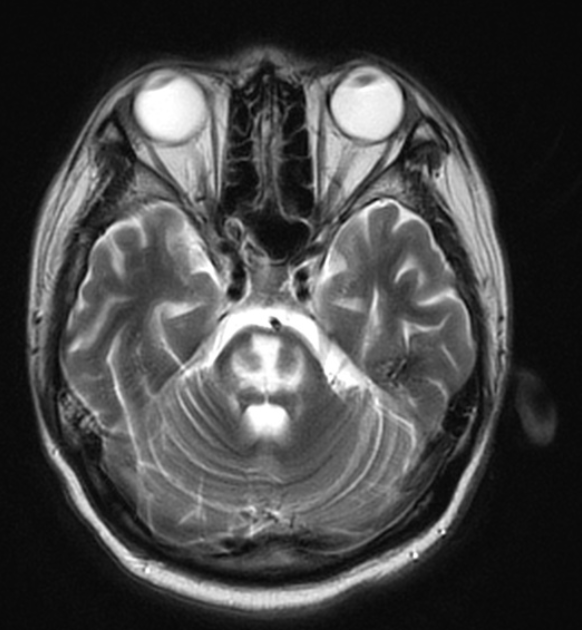

21 y/o M with Type I DM presents with abdominal pain, dehydration, and hyperventilation. DXT=450. After aggressive administration of insulin and fluids, the patient develops altered mental status and seizures. The following MRI is obtained, confirming your suspicion of this syndrome.

What is Osmotic Demyelination Syndrome (previously Central Pontine Myelinolysis)?